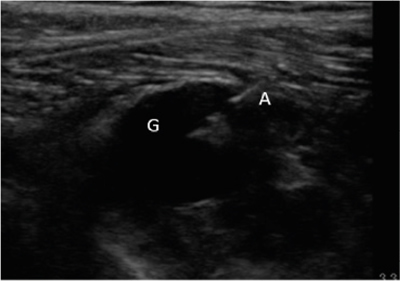

Se diagnosticó, por lo tanto, paresia de nervio peroneo derecho secundario a compresión por ganglión de articulación tibio-peronea proximal y se propuso al paciente un manejo intervencionista del mismo, que aceptó. Se realizó drenaje ecoguiado empleando una sonda lineal de alta frecuencia (10-5 MHz), una aguja de 20 G y una jeringa roscada de 5 ml (Figura 2), retirándose sin dificultad 1,5-2 ml de contenido mucinoso compatible con ganglión. Posteriormente se realizó infiltración de 1 ml de triamcinolona 40 mg ml diluida en 0,5 ml de mepivacaína al 2 %. Tras el procedimiento se evidencia una clara disminución del tamaño del ganglión.

Fig. 2. Ecografía en corte longitudinal de aspiración con aguja ecoguiada del ganglión. G: ganglión. A: aguja en interior de ganglión iniciando aspirado.